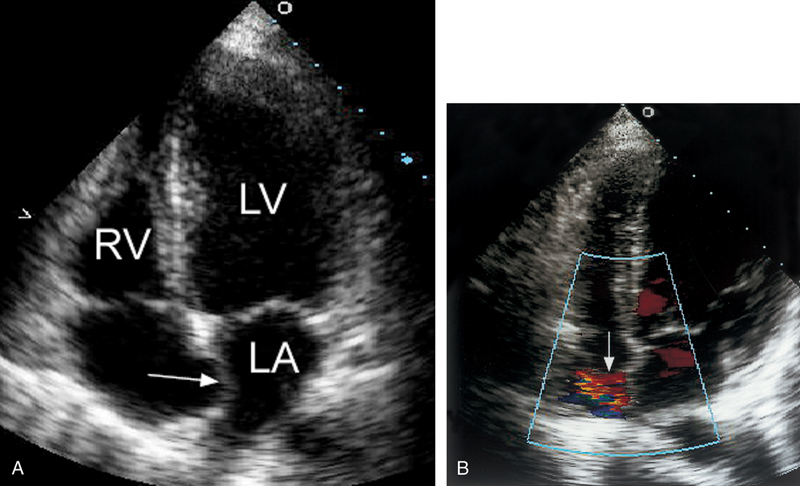

فحوصات تشخيصية لبعض امراض القلب والشرايين التاجية